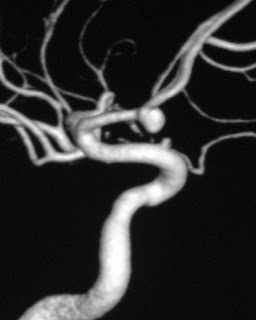

SAH angiogram

The aneurysmal pouch is composed of thickened hyalinised intima with the muscular wall & internal elastic lamina being absent.

* size : ideally 3 axis maximum size meansurements

* neck : maximal width of the neck of the aneurysm

* shape and lobulations

* orientation : the direction in which the aneurysm points is often important in both endovascular and surgical planning

This small berry aneurysm projecting inferiorly from the ACOM had pushed into the optic chiasm causing a bitemporal hemianopia, similar to that seen in pituitary lesions.